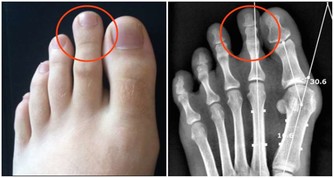

膝關節尤其是人體所有關節、軟骨構造中最為複雜的部位,

包括髕骨、大腿股骨、小腿脛骨、兩個半月狀軟骨及四條韌帶,活動機轉相當複雜。

加上膝關節必須承受人體全部或數倍的重量,

加上日常跑、跳、上下樓梯、背負重物、穿高跟鞋等因素,

膝蓋的受力更大,是全身關節中最容易退化的部位。